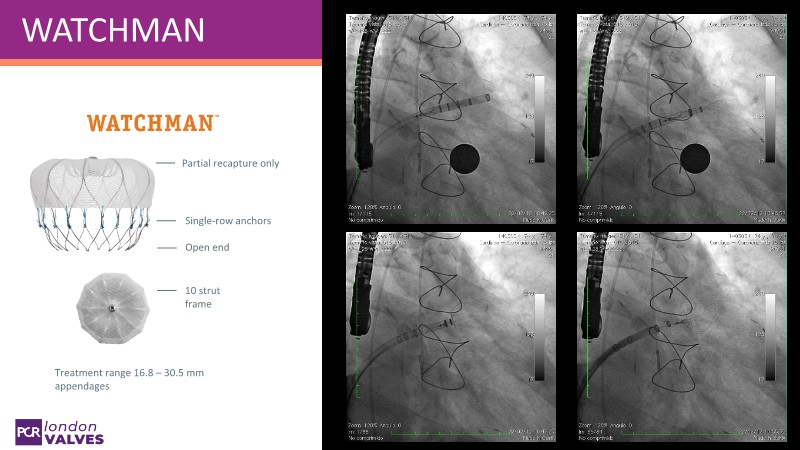

Explore the forefront of left atrial appendage (LAA) closure with this session focusing on the latest innovations and clinical opportunities. Topics include recent data on WATCHMAN FLX PRO and VersaCross Connect systems, workflow strategies to improve procedural efficiency, and discussions on upcoming clinical trials such as CHAF and LAAOS IV, emphasizing expanding stroke prevention options beyond bleeding risk reduction.

- To review the latest data on WATCHMAN FLX PRO and VersaCross Connect - HEAL LAA and subanalysis

- To learn workflow strategies to improve efficiencies for LAA closure - VersaCross Connect + PRO + TruSteer